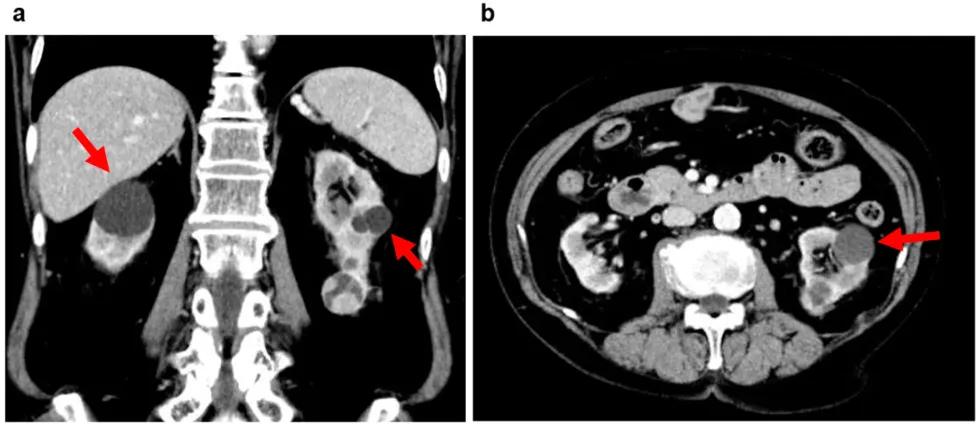

Diagnostikimi është i thjeshtë dhe shpesh i rastësishëm, pasi cistet zbulohen gjatë ekzaminimeve të kryera për arsye të tjera. Ekografia është zgjedhja e parë, sepse tregon qartë nëse cisti është e mbushur me lëng, ndërsa CT-ja dhe rezonanca magnetike ndihmojnë më tej në dallimin e cisteve nga masat solide.

Veçanërisht e rëndësishme është vlerësimi i pamjes së murit të cistit, prania e kalcifikimeve dhe rregullsia e kufijve, sepse këto karakteristika përcaktojnë rrezikun e malignitetit.